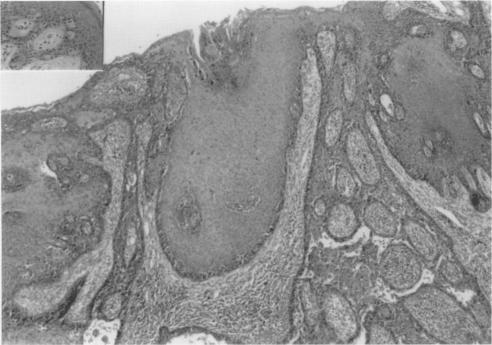

Extramammary Paget disease of the vulva was found in association with vulval adenocarcinoma in an elderly woman who also had a uterine prolapse. The characteristic histological appearances of extramammary Paget disease were masked by striking reactive changes in the squamous epithelium. Primary excision of both the intraepithelial and invasive disease appeared complete. However, a subsequent hysterectomy with repair of the prolapse revealed extramammary Paget disease in the upper vaginal mucosa and cervix, a finding which is very rarely described. Pathogenesis and diagnosis of extramammary Paget disease is discussed, with differential diagnosis and reference to immunohistochemical methods.

在外阴脱垂的老年女性中,发现外阴部乳房外佩吉特病与外阴腺癌相关。乳房外佩吉特病的典型组织学表现被鳞状上皮显著的反应性改变所掩盖。上皮内病变和浸润性病变的初次切除似乎是彻底的。然而,随后的子宫切除术及脱垂修复术显示,阴道上段黏膜和宫颈存在乳房外佩吉特病,这一发现很少被描述。本文讨论了乳房外佩吉特病的发病机制和诊断,并提及鉴别诊断及免疫组化方法。